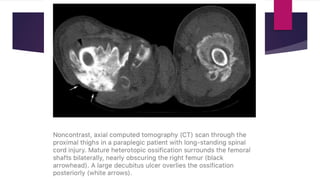

 CT scan – Reveals zonal phenomenon with a rim of calcification of

varying thickness at periphery while central area similar to muscle.

 Always develop below level of injury.

 Hips are the most common site.

 The disease is often more extensive involving various sites together.